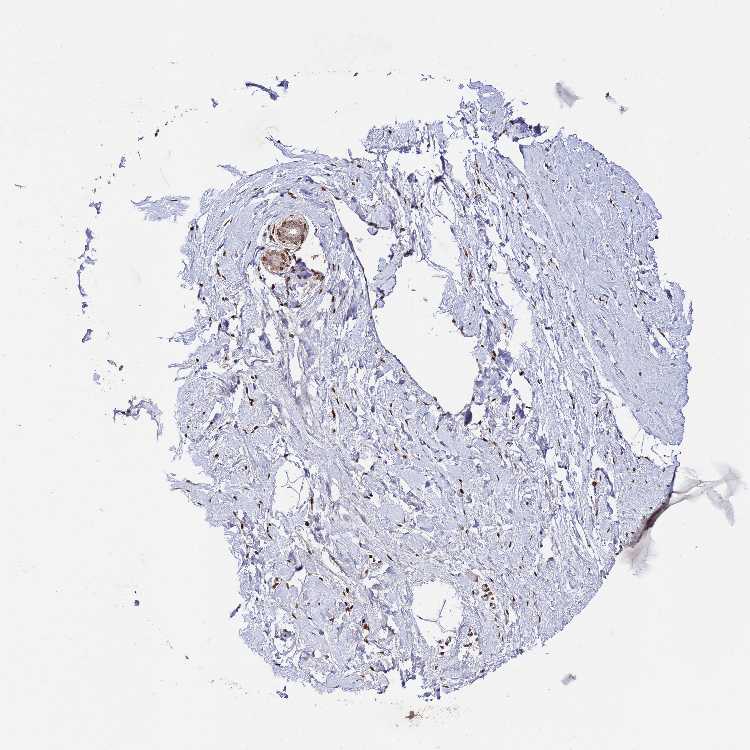

BREAST - Antibody stainingi

Antibody staining in the annotated cell types in the current human tissue is reported as not detected, low, medium, or high, based on conventional immunohistochemistry profiling in selected tissues. This score is based on the combination of the staining intensity and fraction of stained cells.

Each image is clickable and will lead to virtual microscopy that enables deeper exploration of all samples and also displays staining intensity scores, fraction scores and subcellular localization as well as patient and tissue information for each sample.

Antibody HPA045337

Adipocytes Low

Glandular cells Low

Myoepithelial cells High